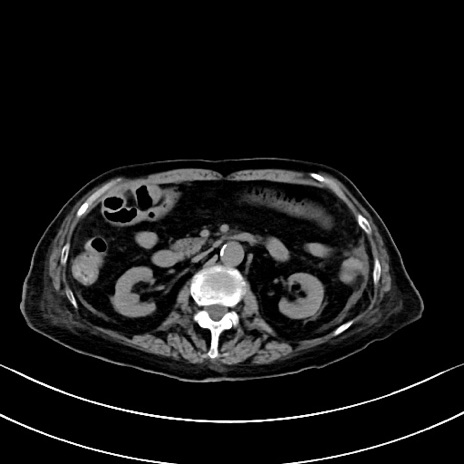

横断像

他院CT